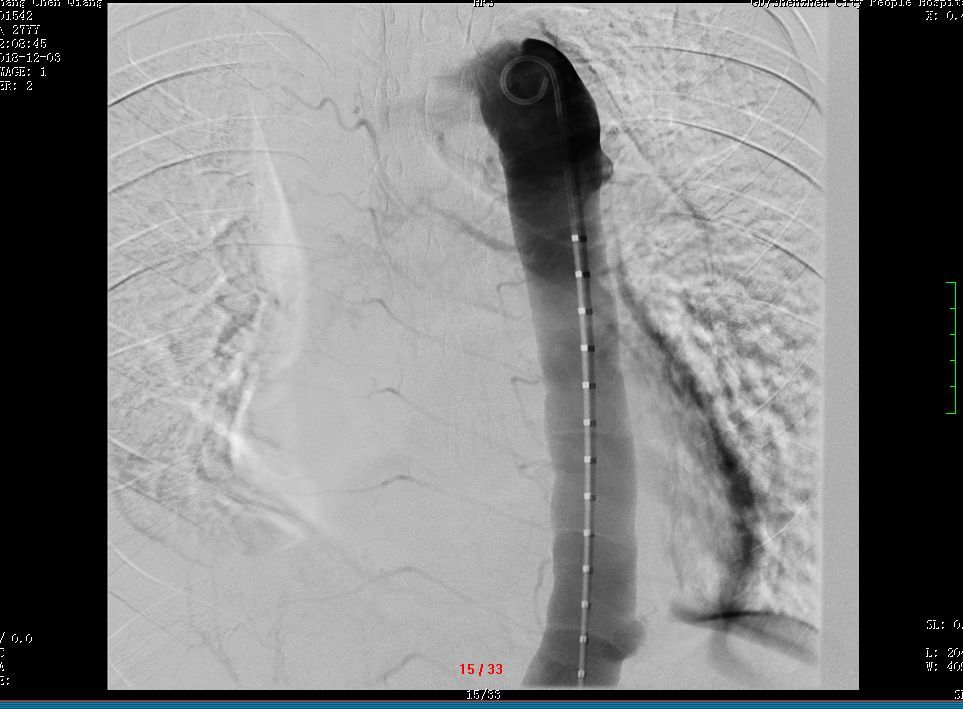

手术当日,陈女士过床后不久,出现呼吸急促、烦躁不安并突发意识丧失及循环障碍。心外科手术团队、麻醉师、手术护士立即协同抢救。

医护团队咬紧牙关、争分夺秒,成功为陈女士实行肺动脉肿瘤摘除术+肺动脉内膜剥脱术,切除的病变送病理检查,回报结果为肺动脉肉瘤!

幸好,术后的陈女士脱离了危险,恢复良好。